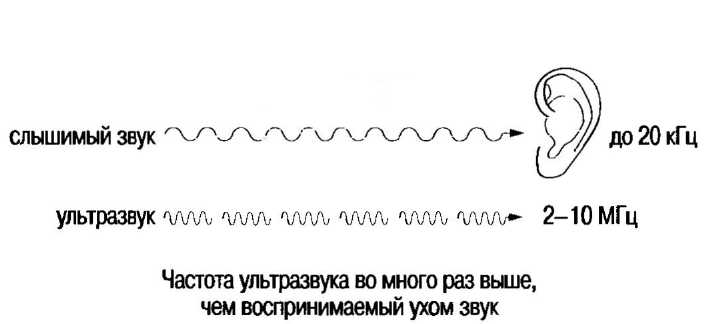

Ультразвуком называются высокочастотные звуковые волны с частотой свыше 20000 циклов в секунду (20 кГц). Эти волны, не воспринимаемые человеческим ухом, могут быть преобразованы в лучи и используются для сканирования тканей тела.

Ультразвуковой импульс, производимый сканером, который описан в данной главе, имеет частоту 2-10 МГц (1 МГц — это 1 000000 циклов/с). Продолжительность импульса составляет 1 микросекунду (одна миллионная часть секунды), импульсы повторяются с частотой 1000 в секунду. Различные ткани по-разному проводят ультразвук: некоторые ткани полностью отражают его, в то время как другие рассеивают сигналы, прежде чем они возвращаются к датчику. Волны проводятся через ткани с различной скоростью (например, 1540 м/с — это скорость распространения ультразвука в мягких тканях).